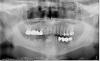

Вообщем, есть вот такая челюсть (моя :-) с мостами, дышащими на ладан (думаю, что их надо убирать). http://s16.radikal.ru/i191/1007/04/d64ef4b5c33e.jpg

Задача: по уму поставить где надо импланты, коронки (где лучше поставить именно их), чтобы о теме зубов забыть очень надолго (в идеале на всю жизнь. А жить я планирую долго :-) ).

снимок хороший,работа большая и интересная с разными заковырками и подводными камнями...сразу Вам говорю-работа не бюджетная!а самое главное нужно Вас смотреть и считать на месте...посмотрев и потрогав руками... с уважением...